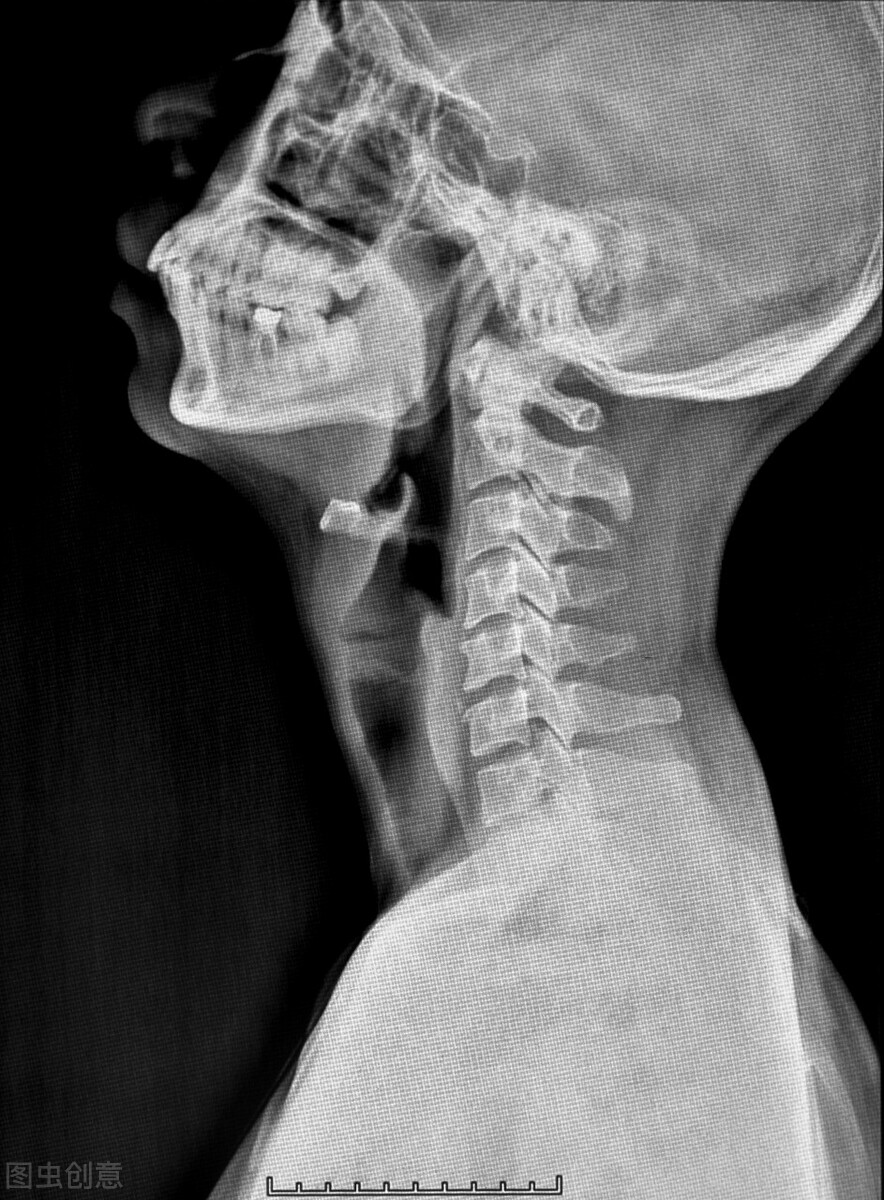

这种情况持续了一些时间,王女士只能到医院寻求医生的专业帮助,最后检查出的结果令王女士大吃一惊,她被诊断为“交感型颈椎病”,她有些难以理解,颈椎病不是脖子上的问题吗?为什么会影响到脑子呢?今天我就来和大家详细说说颈椎病为什么会影响到脑子!

颈椎病是一种由于椎间盘退行性改变导致的疾病,比如需要长期伏案工作的人群,他们的颈椎就会慢性劳损,从而导致颈椎超过颈肩能承受的压力,产生累积性损伤,这是目前导致年轻人患上颈椎病最常见的原因。